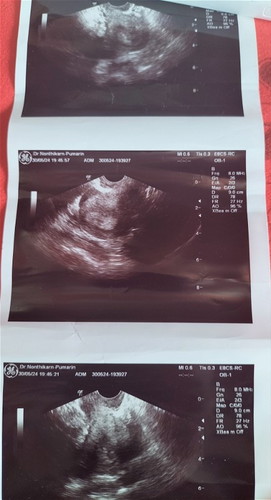

พ.ค 3-5ประจำเดือนมาแต่น้อยอ้วกเวียนหัว กินไม่ได้ 17ตรวจยังขีดเดียว พอ19ตรวจ2ขีดจางๆ กี่อันก็เหมือนกัน 30พ.ค ไปคลินิกอันตร้าซาวด์เจอถุงตั้งครรภ์3สัปดาห์กว่าๆ พอมาตอนนี้มีเลือดออกเหมือนประจำเดือนเลยค